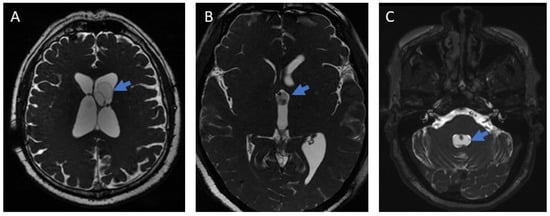

Comparison of Effectiveness Between Cysticidal and Surgical Treatments in Patients with Intraventricular Neurocysticercosis: A Single-Center Experience

Neurocysticercosis (NCC) remains a major public health problem in endemic countries. Clinical manifestations and therapeutic strategies vary depending on the location of the parasite. While the benefits of cysticidal treatment are well established for parenchymal and subarachnoid NCC, the optimal management of intraventricular NCC (IVNCC) remains controversial. We conducted a retrospective study of 51 patients: 37 (72.54%) received cysticidal treatment as initial therapy and 14 (27.45%) underwent neurosurgical intervention. Although six months after treatment, the proportion of patients with inactive disease was higher in the surgical group, no significant difference was observed after one year. Patients in both groups showed significant improvement in functionality as measured by the Karnofsky Index (KI), with no significant difference between groups. These results are consistent with cysticidal treatment being a valid therapeutic option for IVNCC, with the choice of management largely determined by the available medical infrastructure and the degree of specialization of healthcare personnel. Full article

Figure 1